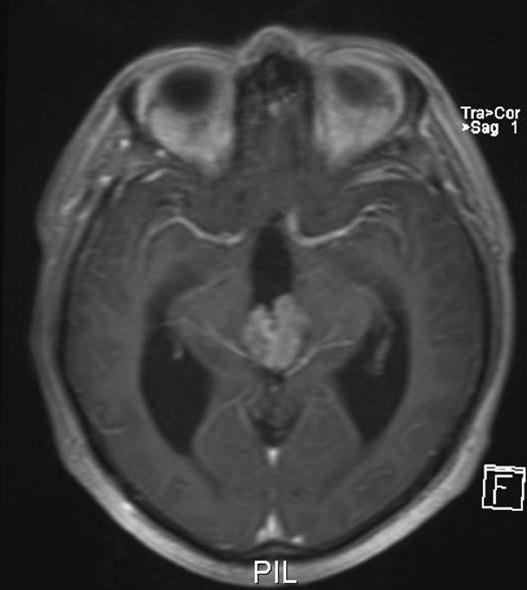

Pineocytom, aksialt snitt

Gjengitt med tillatelse av Radiologisk avdeling, Universitetssykehuset Nord-Norge